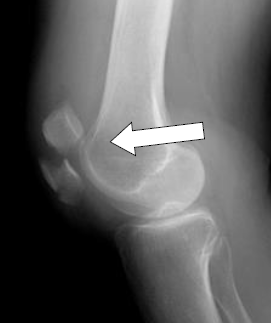

• رادیوگرافی (اشعه ایکس): برای تایید دررفتگی، بررسی موقعیت کشکک و رد کردن شکستگی های همراه استفاده میشود.

• مکانیسم آسیب: دررفتگی زمانی اتفاق می افتد که این استخوان به طور کامل از شیار خود خارج شود. در بیشتر موارد، کشکک به سمت بیرون زانو جابجا میشود. گاهی اوقات نیز کشکک پس از دررفتگی، به طور خودبه خود به جایگاه اصلی باز میگردد که به آن “دررفتگی گذرا” میگویند.